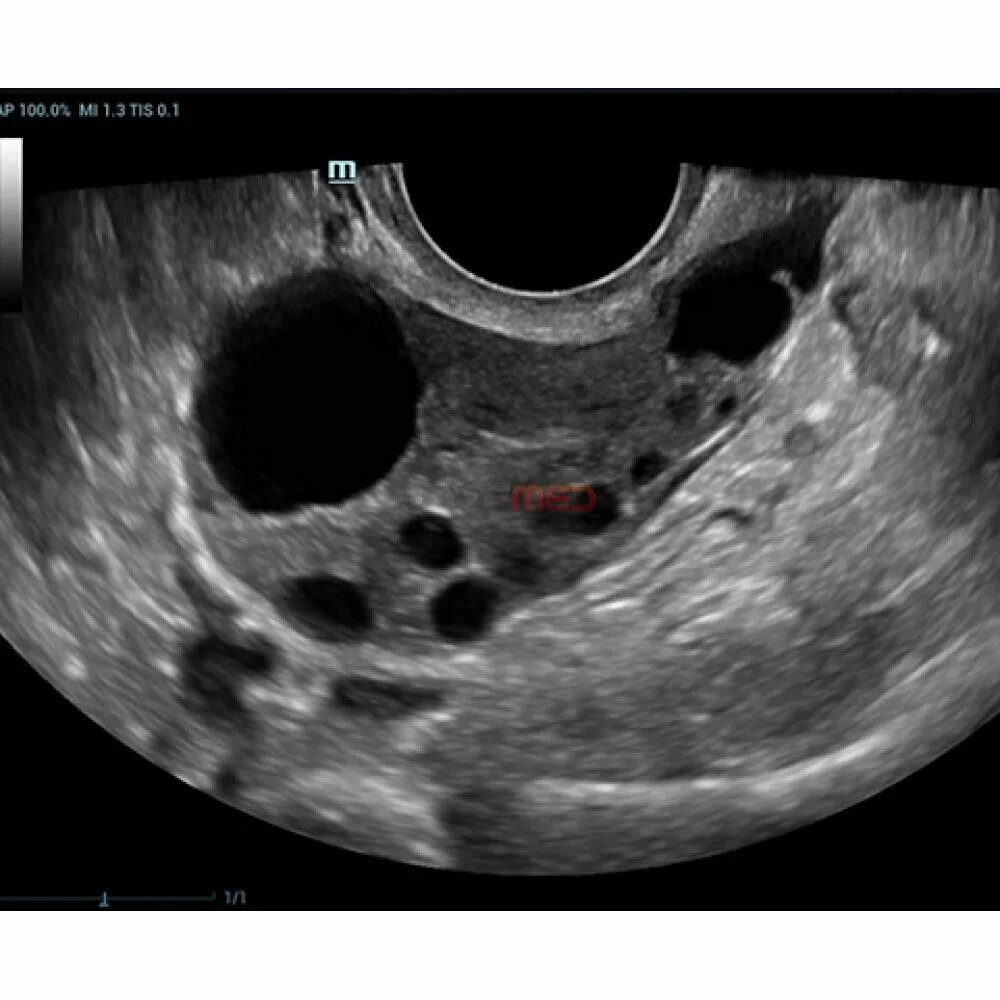

Неовулированный фолликул